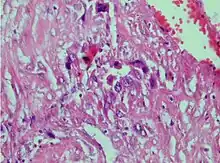

| Photomicrograph showing proliferating intermediate trophoblast with scarce cytotophoblastic and syncytiotrophoblastic elements | |

A placental site trophoblastic tumor is a monophasic neoplasm of the implantation site intermediate trophoblast, and usually a benign lesion, which comprises less than 2% of all gestational trophoblastic proliferations. Preceding conditions include molar pregnancy (5%). Compared to choriocarcinoma or invasive mole, hemorrhage is less conspicuous and serum β-HCG level is low, making early diagnosis difficult.

Immunohistochemistry: Often stains with hPL, keratin, Mel-CAM, EGFR.